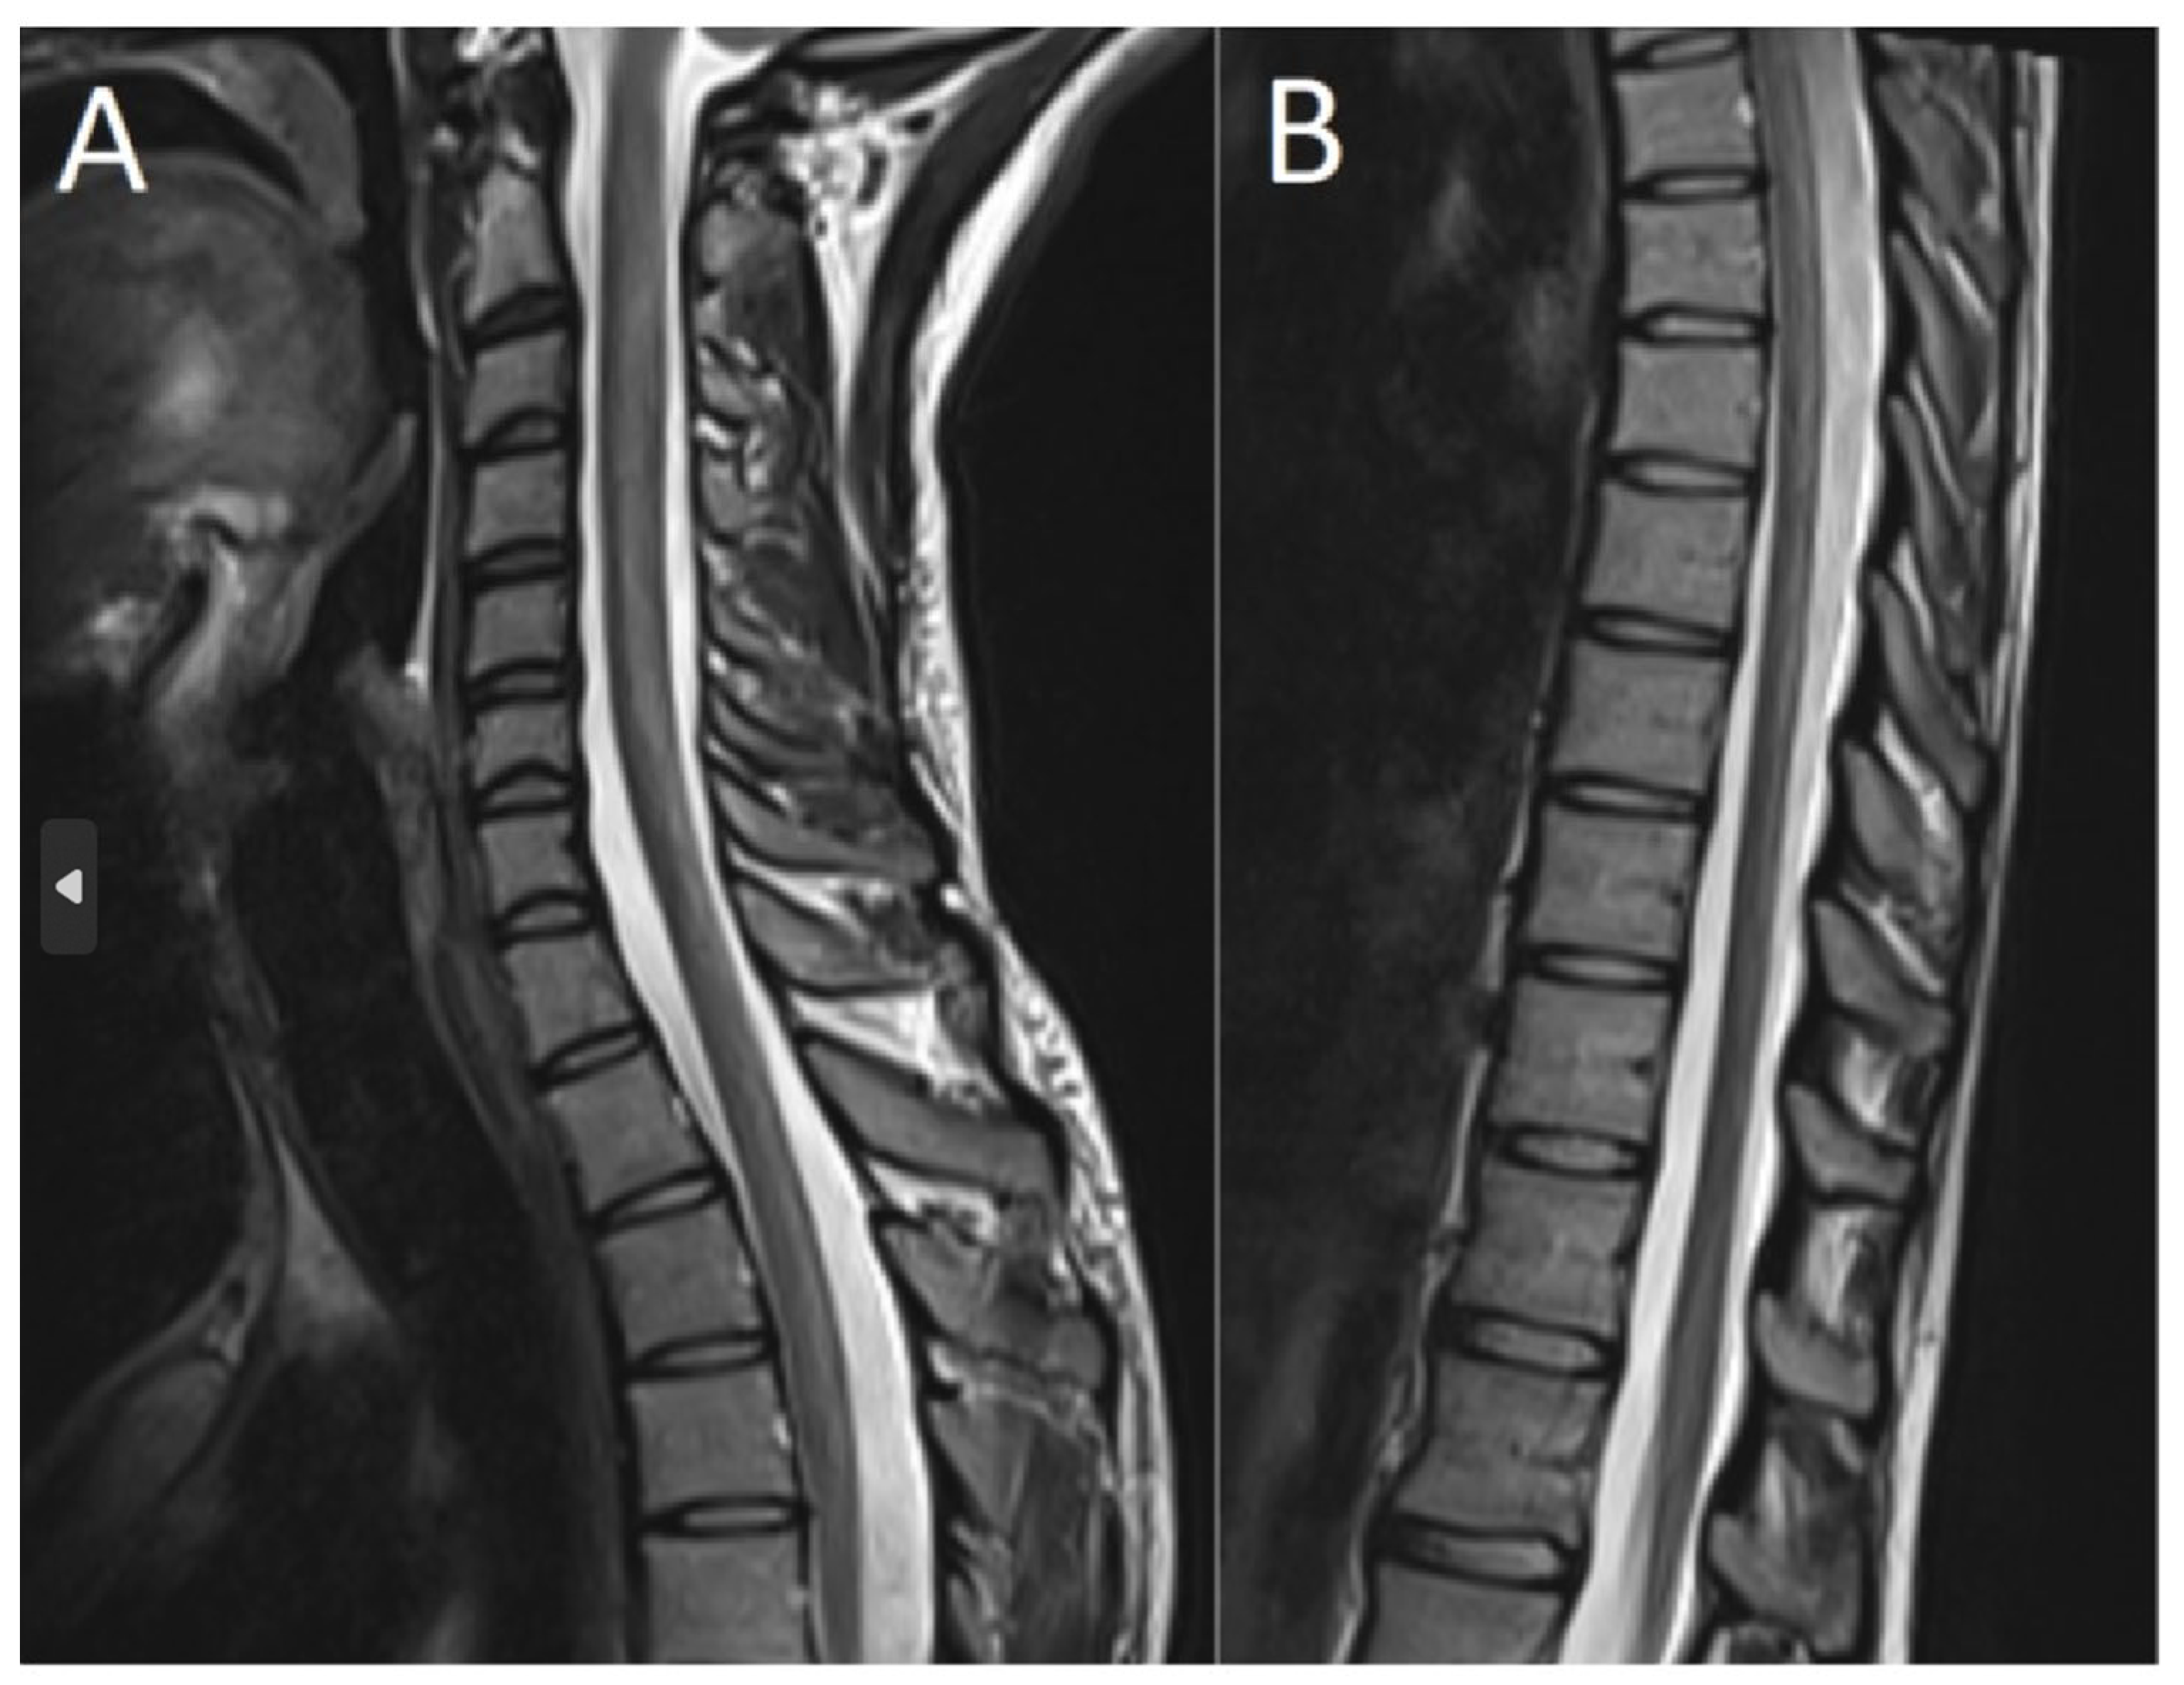

2. Case Description